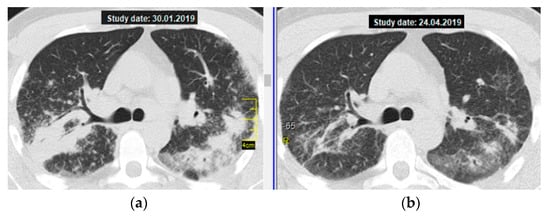

As an illustration, below you can find a brief description of the successful treatment with MTX 15 mg/week in a 27-year-old patient with severe sarcoidosis—massive consolidations in lungs, respiratory failure (MRC 3), and moderate impairment of pulmonary ventilation and diffusion capacity of the lungs. At the same time, the patient had subcompensated diabetes mellitus, which excluded the possibility of CS therapy.

The patient underwent monotherapy with MTX at a dose of 15 mg/week. As a result, by the second visit (after 3 months of treatment), a pronounced positive dynamic of subjective symptoms was noted—dyspnea occurred only when performing the usual load (when climbing the stairs to the third or fourth floor), the cough disappeared, and the body temperature returned to normal. Figure 1 shows a thoracic CT scan (axial section at the level of the tracheal bifurcation): the almost complete resolution of consolidations in S3,6 of both lungs is clearly visible.

Figure 1. Pulmonary sarcoidosis, stage II, atypical form—multiple massive consolidations in both lungs; a thoracic CT scan (axial section at the level of the tracheal bifurcation): (a) on the left—before treatment, (b) on the right—regression after 3 months of MTX therapy (15 mg/week).